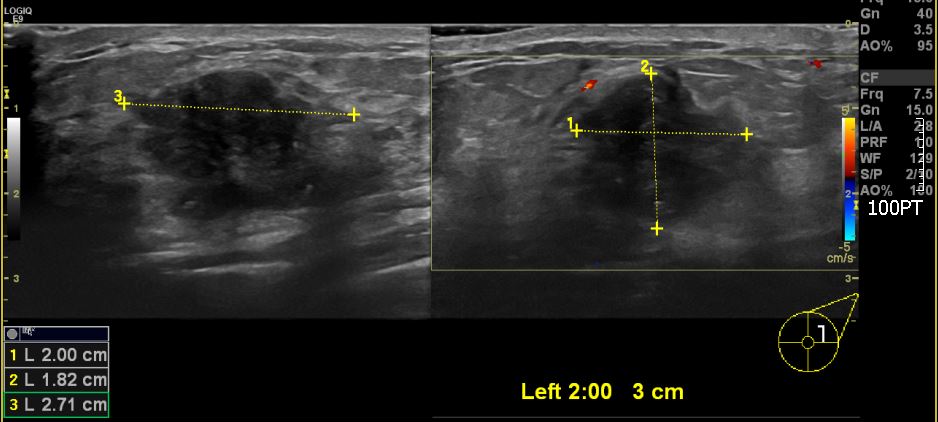

좌측유방에 만져지는 멍우리로 내원하신 50대 환자분이십니다.

본원에서 좌측 2시방향에 혹을 조직검사 시행하였고

침윤성 유관암 진단되었습니다.